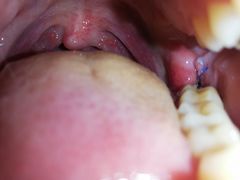

Czy to normalne, że została mi dziura do zębodołu po wyrwaniu ósemeczki, czy mam się z tym udać do skontrolowania? Miał ktoś podobnie po ekstrakcji?

Co do tematu- szwa sama się rozpuści w dziąśle, a dziurę po wyrwaniu jeszcze długo bedziesz miał. Z czasem nawet zapomnisz, że tam jakiś ząb był.

Przerabiałem to dwa razy. Na początku będzie dyskomfort, zwłaszcza w trakcie jedzenia. Często po prostu będzie Ci w tą dziurę wpadało jedzenie. Po kilku miesiącach nie powinno być śladu. Tylnie zęby są większe, naturalnym jest, że zostawią sporych rozmiarów krater po wyrwaniu. :P

Dołek to norma. Ale jeśli boli, to może oznaczać suchy zębodół. Warto to skontrolować.

Czy to normalne, że została mi dziura do zębodołu po wyrwaniu ósemeczki

Tak, to normalne.

Sam miałem w zeszłym roku ekstrakcję zęba z dłutowaniem (czy jak to się zwie), szwy na dziąśle miałem prawie tydzień.